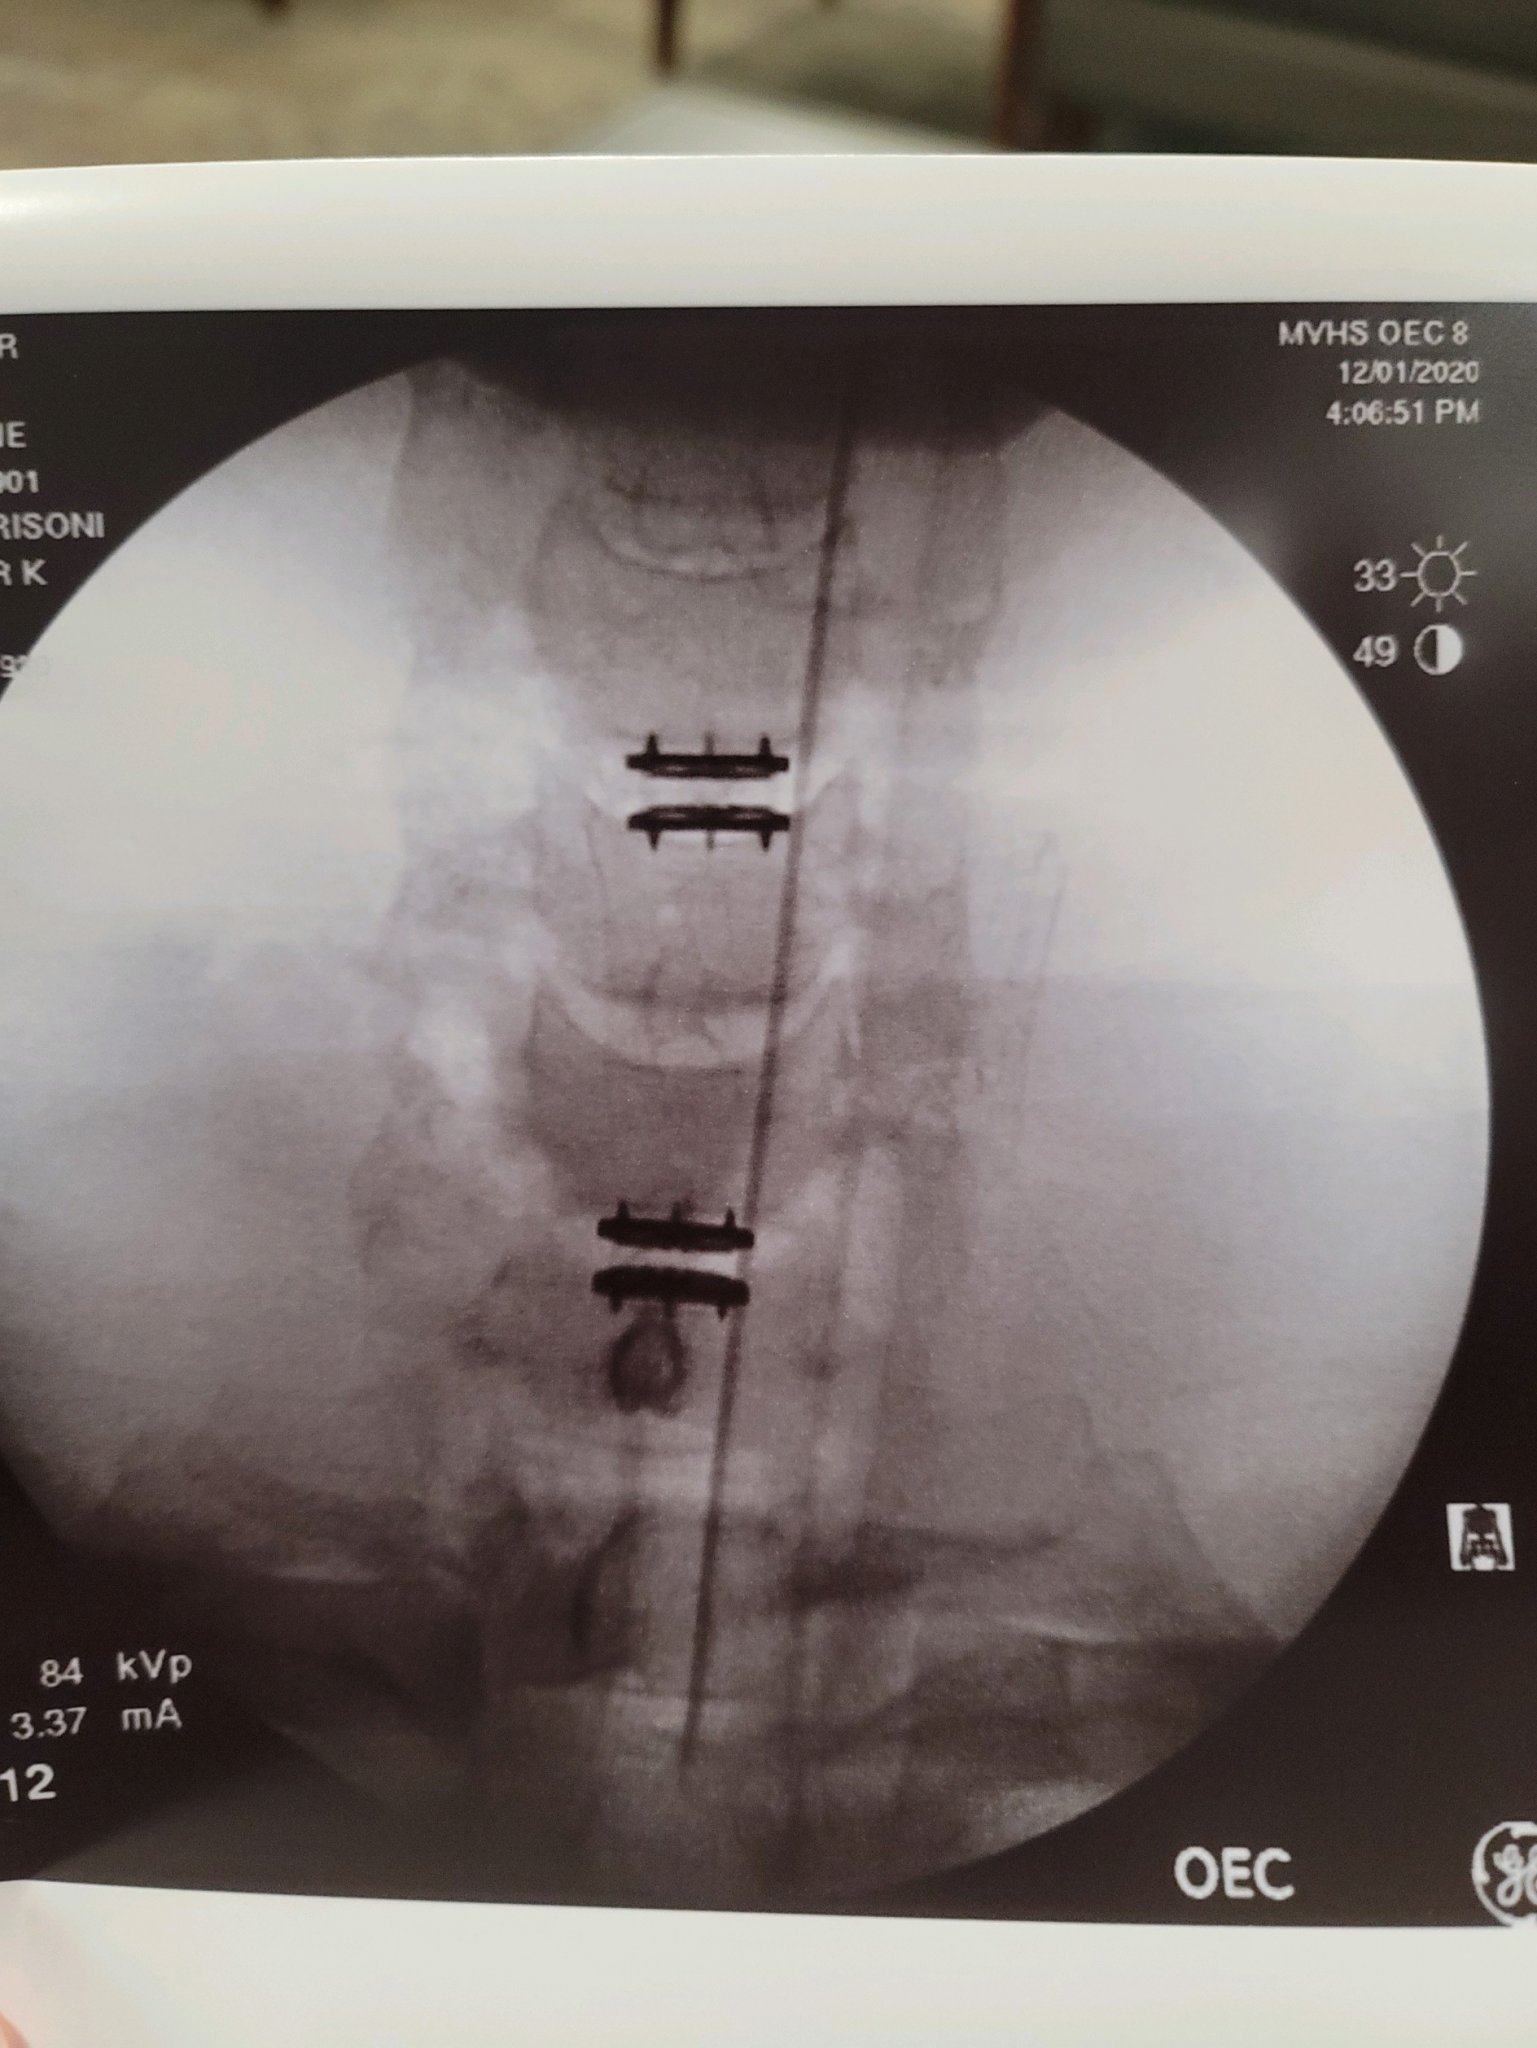

Tired and sore but already notice improvement. Tingling in fingers is gone. Numbness in a couple of fingers, not all of them. The worst part was an hour ago when they pulled the JP drain. Profanity flowed forth freely! View attachment 7489566View attachment 7489563View attachment 7489563View attachment 7489565Heading home for care under the warden... I mean the wifey. I appreciate all the support, thoughts and prayers. Its just one of the reasons I love you beautiful fools.